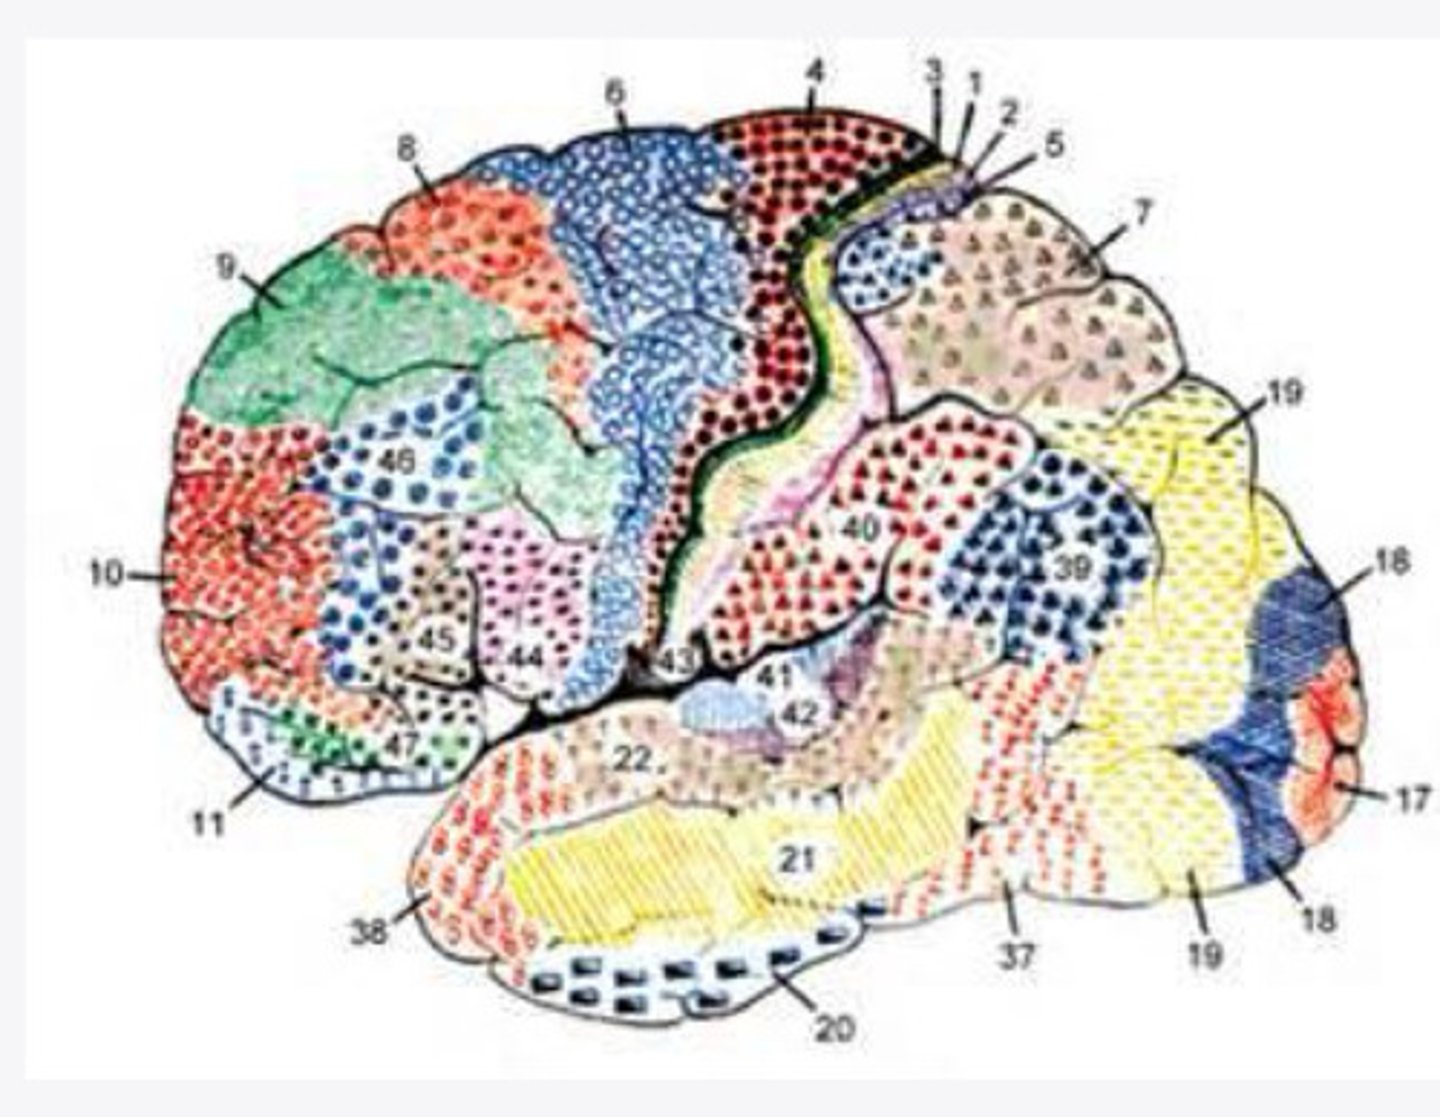

52 Brodmann areas

What are the histological divisions of the cortex of the brain?

cerebral cortex on the basis of histological sections

What did Brodmann study?

52 distinct regions of the cortex based on the thickness of cell layers alone

What did Brodmann find?

2-5

What layers of the cortex of the brain did Brodmann find were variable in histological sections?

function

In the 52 Brodmann areas, structure lens itself to ______

4, 6, 8, 44/45

What are the important Brodmann areas of the frontal lobe?

motor movements

What is the function of Brodmann area 4?

2 and 5

What layers of the cortex are thick in Brodmann area 4?

helps coordinate activity in the motor cortex (opposing muscle groups)

What is the function of Brodmann area 6?

2 and 3

What layers of the cortex are thick in Brodmann area 6?